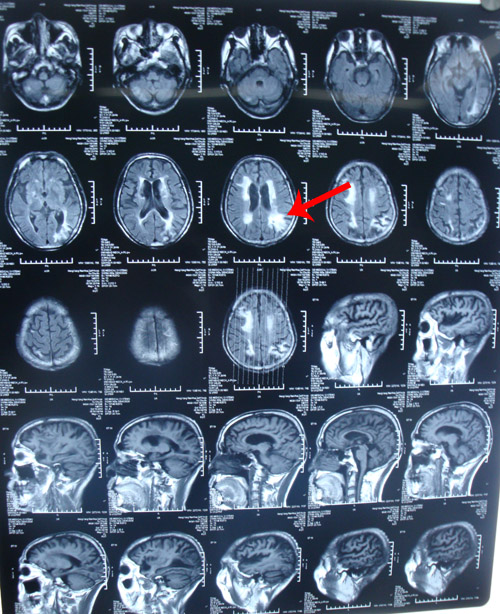

南华大学附一院头颅MRI示:左枕叶内异常信号,考虑脑梗塞可能性大。

该患者为老年男性,有高血压病史,以“后循环症状(反复头晕)”就诊,右侧基底节区陈旧性梗塞灶。造影及DSA检查证实其双侧颈动脉狭窄(右侧重),远端虹吸段亦存在狭窄;右椎动脉串珠样改变。因椎动脉呈串珠杨改变,无法进行手术操作。因此,建议通过手术取出颈动脉病变,改善脑部整体供血,既可避免中风发作,又可以通过侧枝循环改善后循环,缓解头晕症状。